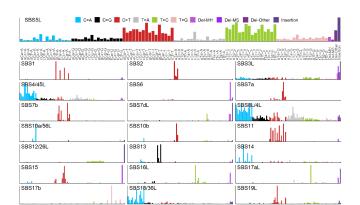

Publicat a Nature Communications

Publicat a Nature Communications

A continuació es mostren alguns projectes destacats que van rebre finançament el 2022 mitjançant convocatòries tant competitives com no competitives per part d’entitats públiques i privades. Aquests i altres projectes estratègics han pogut avançar gràcies a l’ús de tecnologies d'última generació, com ara l'aprenentatge automàtic, la intel·ligència artificial i la seqüenciació de cèl·lules úniques.